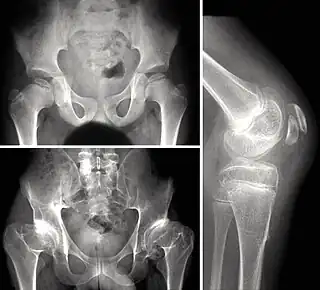

Las pruebas radiológicas suelen ser la clave del diagnóstico.[2] Es recomendable confirmar el diagnóstico con una prueba genética que confirme el tipo de displasia. Los centros de osificación epifisarios suelen aparecer tarde, (retraso de edad ósea), y aparecen con una forma irregular, o incluso fragmentados, en las formas más graves. Muy importante comprobar que la afectación es múltiple.

- Caderas: La epífisis proximal del fémur se deforma, aplanándose, con parecido a una coxa vara. Aparece artrosis precoz, aunque sin quistes periarticulares.

- Rodillas: Cuadrangulación de los cóndilos del fémur. También es frecuente el genu valgo, (pudiendo ser planteable una osteotomía correctora).